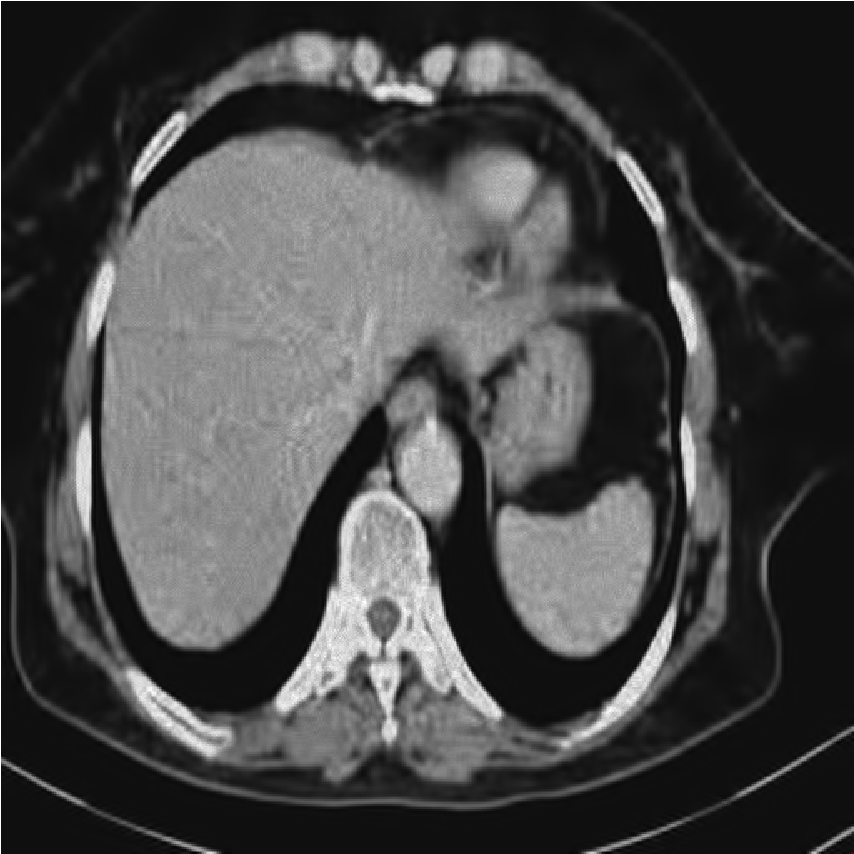

We performed extensive numerical simulations to examine the performance of the aforementioned denoising methods. For this purpose, we used a pixel grayscale CT scan image, shown in Fig. 2a. Noisy versions of this image were created by adding different types of noise at various strengths. The noise types considered are Gaussian noise, uniform noise, salt and pepper noise, and Poisson noise. The following subsections present and explore the results obtained from the various denoising methods. All computational programming were carried out using Mathematica 12.0.

[a)Clean]

This finding highlights a critical principle in image processing: the implementation strategy (global vs. local processing) can be as important as the choice of transform itself. Future work could explore local or adaptive wavelet thresholding schemes (e.g., context modeling, spatially varying thresholds) to leverage the strengths of wavelets while incorporating the local adaptability that made DFCT successful in this study. Figs. 8-11 show visual comparison of denoising results for the four kinds of noise. In the Figs. 8-11 the left image is noisy input image, the middle image is denoised image using the best wavelet method (BIOS wavelet with Hyperbola threshold for case of Gaussian and uniform noise, BIOS wavelet for Poisson noise and Daubechies wavelet with SURELevel for salt-and-pepper noise) and, the right image is denoised using DFCT.